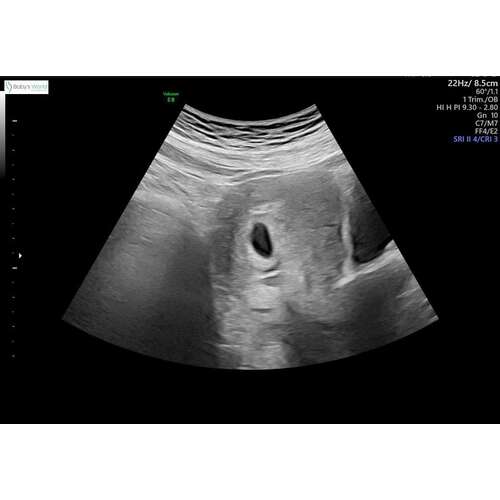

Ik had vandaag ook een goede echo met 6 wk!! Super opgelucht voor nu 😊

Yes!!! Gefeliciteerd 😍 Super blij voor jou! Heb je een foto? Ik moet morgen weer, ben dan rond de 8 weken, ben heel benieuwd!